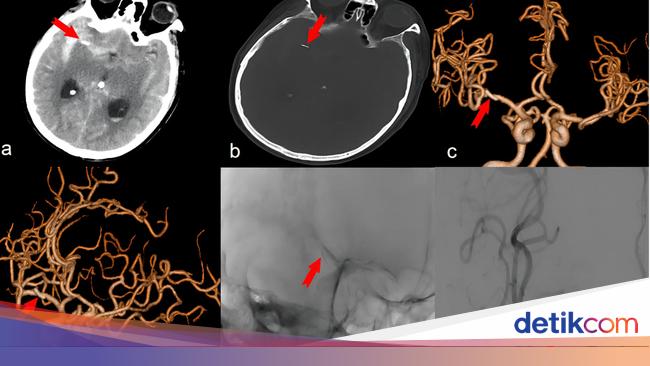

Penampakan Jarum Akupunktur 'Nyangkut' di Otak, Diduga Sudah Ada Selama 20 Tahun

Seorang pria berusia 74 tahun terpaksa dioperasi pada bagian kepalanya setelah ditemukan jarum akupunktur yang tertancap di dalam otaknya. Begini kronologinya.